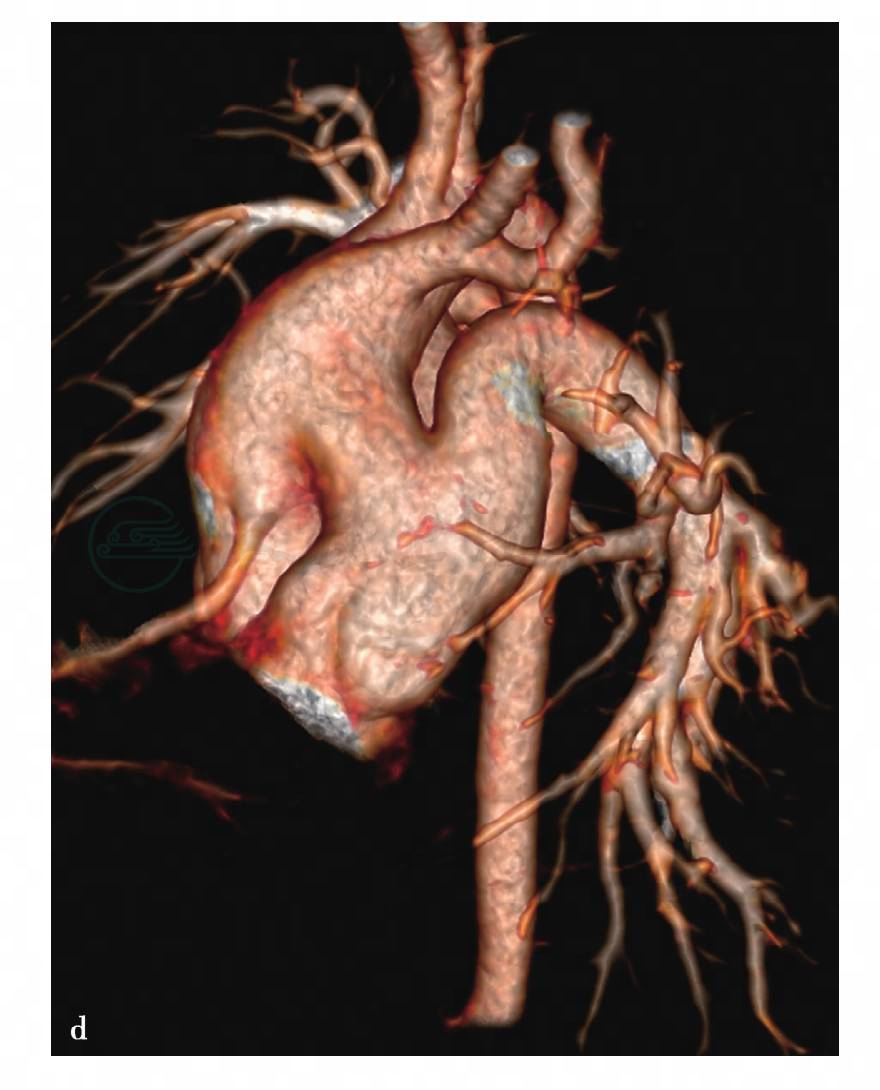

图8 b,胸腹主动脉VR重组图像见主动脉真假腔

图9 d,VR重组图像示主-肺动脉异常通道,右冠状动脉起源于升主动脉侧壁